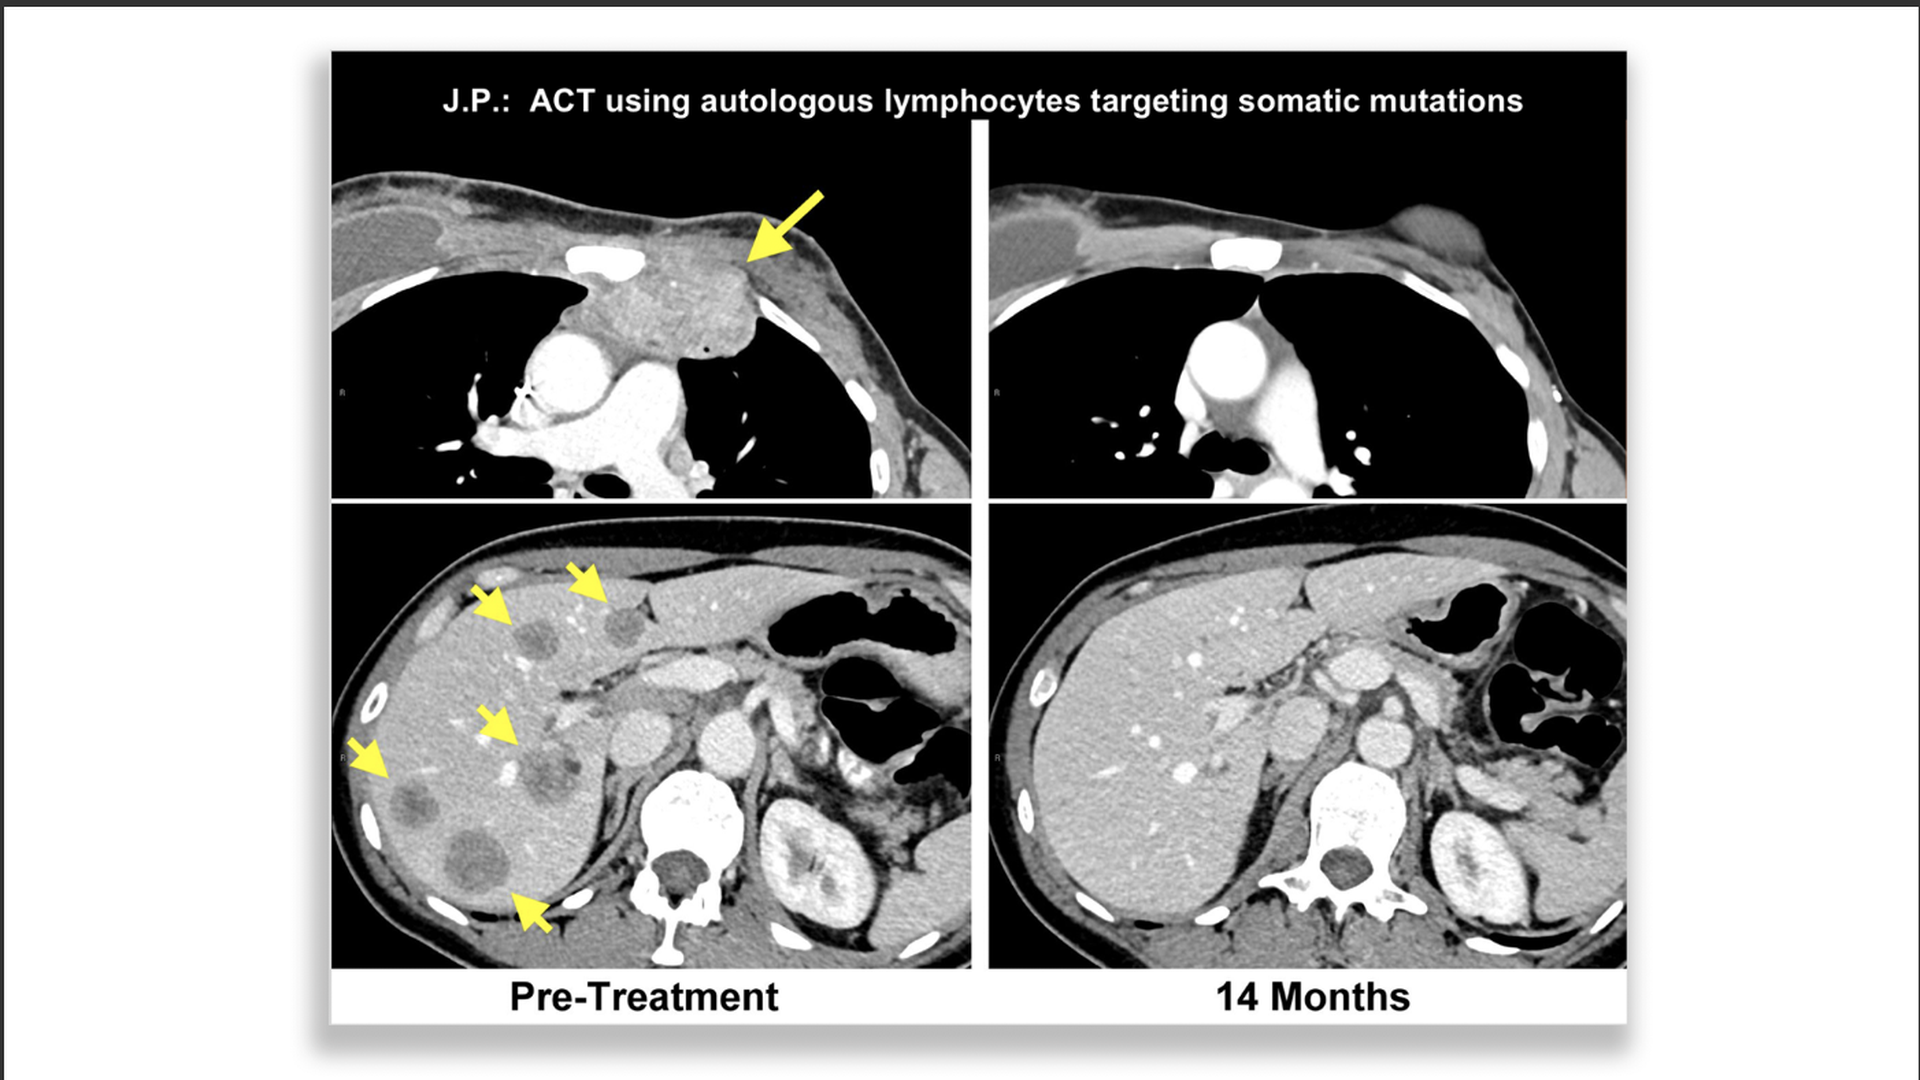

Scan showing breast cancer patient before and after successful immunotherapy treatment

Breast cancer patient who responded to immunotherapy. Left is pretreatment (upper chest wall, lower liver) with yellow arrows pointing to the tumors. Right is after treatment with all tumors gone. Photo: Steven A. Rosenberg/NCI